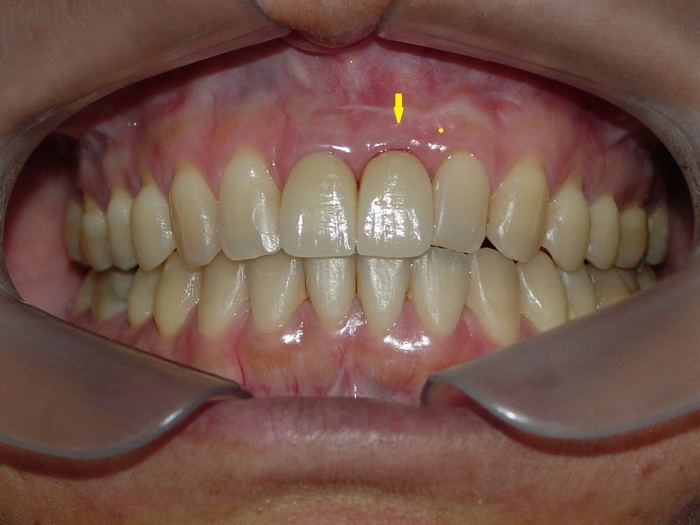

Imagem final do caso terminado em janeiro de 2013

Imagem de 3 meses de controle